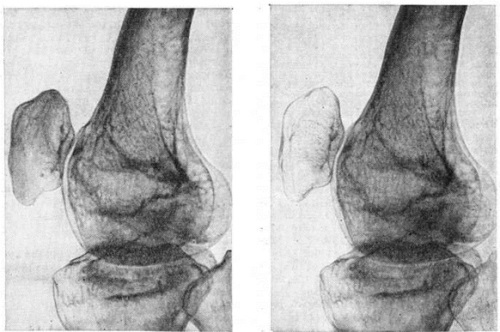

Главным рентгенпризнаком этой патологии выступает пятнистый посттравматический остеопороз.